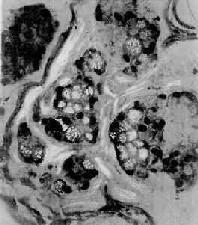

4.粘液癌(mucoid carcinoma)呈腺样结构或单纯癌结构,癌细胞胞浆内出现大量偏酸性粘液,常将胞核挤压于癌细胞浆之一侧,形似戒指,故称之为印戒细胞(signet-ring cell)(图10-19)。粘液癌的恶性度高。此型因癌组织含大量粘液,肉眼上呈半透明的胶冻状故也称胶样癌(colloid carcinoma)。

癌"/>

癌"/>

图10-19 粘液癌

癌细胞成团,胞浆内充满大量粘液,核被挤向一侧,呈印戒状